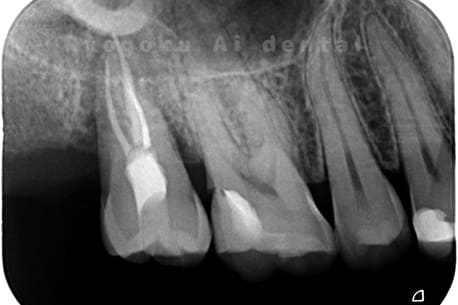

Case03

- 重度カリエス、慢性根尖性歯周炎

- 治療内容

- 自家歯牙移植

- 治療費用

- 220,000円

他院で右下の根の治療を行い、セラミックを被せる説明をされていたが、根の治療が終わらないため転院された患者さんです。隣の親知らずの抜歯の必要性と、根の治療を行なっている歯牙の予後が悪いため、移植治療を提案し、右下の親知らずの抜歯と同時に、右下の奥歯(7番)への移植治療を行いました。被せ物を行う必要もなく、順調に経過してます。

<リスク・副作用>

治療後、痛みや違和感、出血、腫れなどが出る事があります。喫煙者、糖尿病などの方の場合、歯が生着しない場合があります。